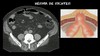

TC = PADRÃO OURO PARA DGTC